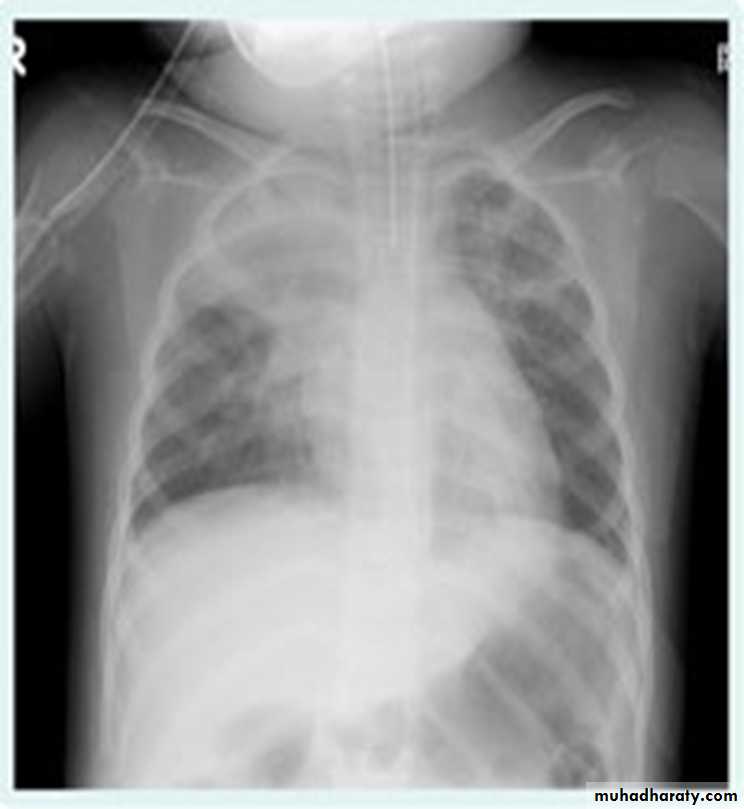

32.RT ML consolidation (pneumonia) ( PA & lat. view )

CXR of adult , PA view on the left and lateral view on the right shows:Triangular Homogenus opacity in the right lower zone (left photo) while in the right photo the opacity occupies middle lobe of the lung.

Indistinct right cardiac border

Loss of the medial aspect of right hemidiphram

Fissures are at normal position

No deviation of the trachea

RT ML consolidation (Pneumonai) (Lat. view )

CXR of adult female , lateral view shows:Homogenus opacity of middle lobe with normal fissures